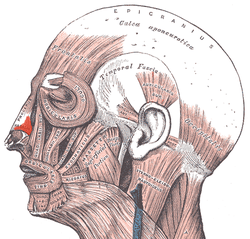

Muscles of the head, face, and neck. (Nasalis labeled at center left.) | |

Position of nasalis muscle (shown in red).